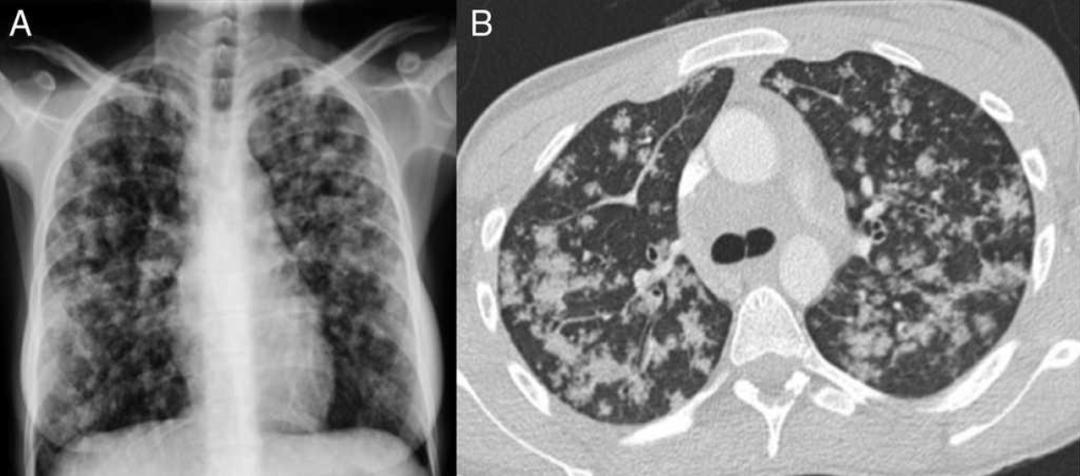

一位19岁女性,有缺铁性贫血史。间断腹痛半年,近3月消瘦10kg,上腹痛伴发热盗汗、干咳1周。胸片及肺CT可见双肺弥漫小结节影,部分融合倾向。3次诱导痰均抗酸菌阳性。[7]

影像中可见斑片结节状的病变相对均匀地弥漫分布于双肺。如果说是沿着气道,又没有明显的树芽症表现,如果说是血行播散,这些病变比一般的粟粒性肺结核又显然粗大的多。所以这个影像是非常特别,有些像转移瘤。但仔细看这些斑片结节几乎都不与胸膜接触,同时其边缘并不清晰光滑而是呈开花状,提示它的本质很可能是小叶中心性结节。